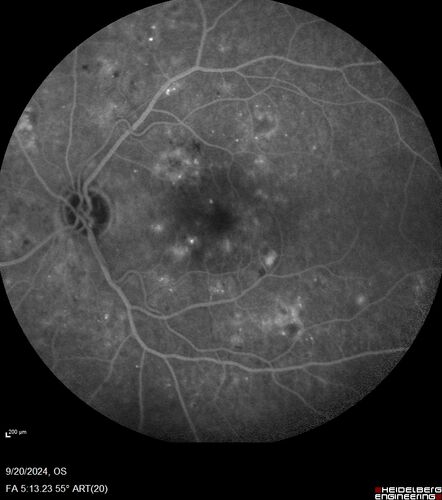

Severe NPDR

53 year old man with blurred vision (needs glasses).

Diabetic for 10 years with poor control

VA 20/32 OU